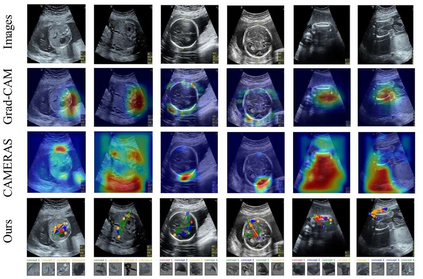

Although deep neural networks (DNN) have achieved state-of-the-art performance in various fields, some unexpected errors are often found in the neural network, which is very dangerous for some tasks requiring high reliability and high security. The non-transparency and unexplainably of Convolutional Neural Networks (CNN) still limit its application in many fields, such as medical care and finance. Despite current studies that have been committed to visualizing the decision process of DNN, most of these methods focus on the low level and do not take into account the prior knowledge of medicine. In this work, we propose an interpretable framework based on key medical concepts, enabling CNN to explain from the perspective of doctors' cognition. We propose an interpretable automatic recognition framework for the ultrasonic standard plane, which uses a concept-based graph convolutional neural network to construct the relationships between key medical concepts, to obtain an interpretation consistent with a doctor's cognition. Extensive experiments have empirically shown that our model can meaningfully explain the decision of the classifier and provide quantitative support.